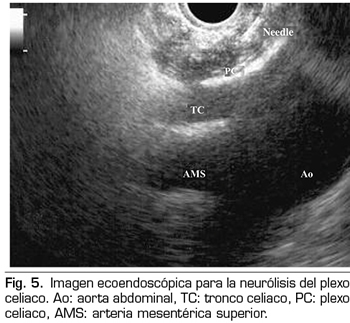

NEURÓLISIS ECOENDOSCÓPICA DEL PLEXO CELIACO

La ecoendoscopia ofrece la ventaja de una mayor visualización del plexo celiaco a corta proximidad, permitiendo una mayor precisión y seguridad en la administración del agente neurolítico y evitando la inyección en estructuras vasculares mediante el uso del Doppler (37) (Figura 5). No obstante, los trabajos que apoyan la neurólisis ecoendoscópica, considerada al igual que la técnica percutánea como una terapia de rescate, están limitados a estudios retrospectivos no controlados (38). Pauli y cols. publicaron un metanálisis que concluye que esta técnica consigue una reducción del dolor del 80 % en pacientes con cáncer de páncreas (39). Algunos estudios muestran un ligero descenso en el consumo de opioides, pero sin una fuerte evidencia científica.